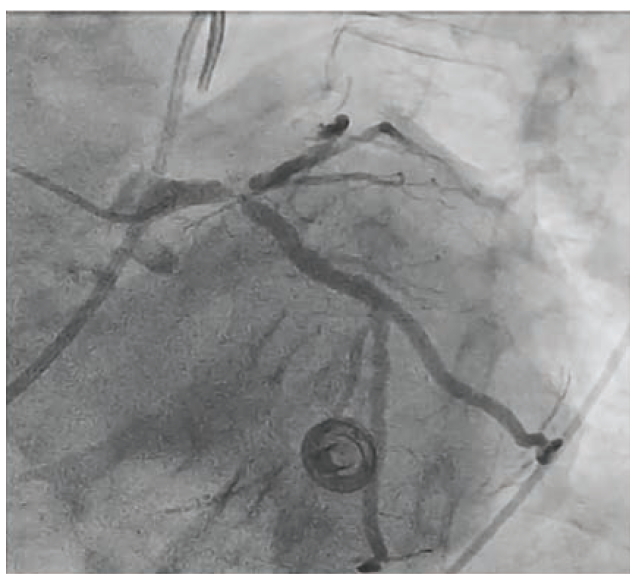

To illustrate this point, we present the case of an 86-year-old male with diabetes mellitus, paroxysmal atrial fibrillation (anticoagulated with apixaban), hypercholesterolemia, and left bundle branch block who presented to the emergency department with acute onset chest pain, shortness of breath and hypotension with a blood pressure of 88/62 mmHg. The patient was diagnosed with non-ST-elevation myocardial infarction (NSTEMI) and was emergently transferred to the cardiac catheterization lab, where the patient underwent left and right heart catheterization. Right heart catheterization demonstrated low cardiac output with elevated filling pressures. Coronary angiography revealed a codominant system, calcified Medina 1,1,1 critical left main disease, and ostial right coronary artery (RCA) disease (Figure 1).